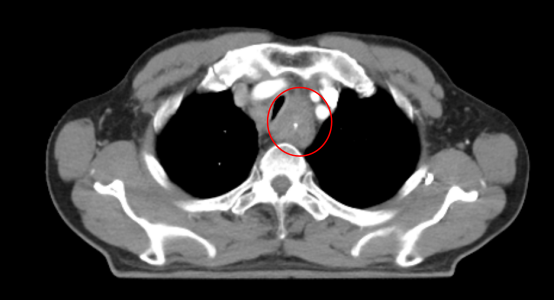

警惕饮食雷区 这些习惯可能是食管癌“元凶” 你中招了吗? 从食管的结构分布来看,主要分为颈部、胸部、腹部 3 段,而食管中的狭窄处因为直径较小,更易与食物发生摩擦,造成一定程度的机械性损伤,长此以往,这些不良饮食习惯容易引发慢性炎症或损伤,成为食管癌的幕后推手。 1、高盐饮食 长期摄入高盐食物可能导致胃酸分泌增多,增加胃黏膜的刺激,从而增加食管癌的风险。 2、腌制食品 腌制食品中含有大量的盐分和亚硝酸盐,这些物质在体内代谢产生亚硝胺类化合物,具有致癌作用。 3、热食烫饮 长期食用过热的食物或饮料可能导致食管黏膜反复烫伤,引起炎症和损伤,增加食管癌的发生风险。 4、缺乏膳食纤维 膳食纤维有助于维持肠道健康,促进肠道蠕动,减少食物在肠道中的停留时间,从而降低食管癌的风险。 总之,食管黏膜上皮肿瘤的发生是多种因素联合作用、长期慢性刺激的结果。 对于食管癌的高危人群,如年龄超过40岁、有长期吸烟饮酒史、饮食习惯不佳的人群,以及有食管癌家族史的人来说,更应该重视体检和筛查。通过定期的胃镜检查、食管细胞学检查等手段,可以及时发现食管黏膜的异常情况,从而做到早发现、早治疗。 案例分享:面对不可手术的食管癌 根治性放化疗成最后希望 * 病 情 介 绍 * 患者姓名:李先生(化名) 年龄:65岁 性别:男 诊断:食管癌(T4N1M0,ⅢB期) 临床表现: 主诉:吞咽困难,体重下降15公斤。 食管镜检查:食管中段可见肿块,阻塞大部分食管腔。 病理活检:报告为鳞状细胞癌。 CT扫描:食管中段肿块,周围淋巴结明显肿大,无远处转移。 (治疗前) 治疗方案: 鉴于患者的年龄、身体状况以及肿瘤的分期,手术切除风险较高,因此选择采用适型调强放疗(IMRT)配合化疗作为主要治疗手段。 治疗效果: 经过6周的放化疗,复查CT显示肿瘤体积显著减小,食管通畅。 随访: 治疗结束后,患者症状明显缓解,能够自行进食。 (治疗两月后食道明显扩张,进食通畅) 总的来说,对于不可手术的食管癌患者,根治性放化疗能够在最大程度上消灭肿瘤细胞,达到缩小肿瘤、疏通食管的目的,让患者重拾自主进食的能力,这不仅极大地改善了患者的营养状况和生活质量,而且在一定程度上延长了患者的生存期。